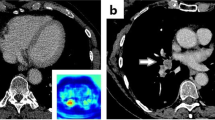

Per study, 16 studies had a reported iPE while 59 studies had an unreported iPE (total iPE prevalence 4.0%). Unreported iPE had a significantly lower number of involved vessels compared to reported iPE, with a median of 2 (IQR 1–4) versus 5 (IQR 3–9.75), p < 0.001 (Fig. 2a). Of the unreported iPE, 32/59 (54.2%) were proximal to the subsegmental arteries. In subsegmental and segmental iPE, the embolic burden varied between 1 and 7 involved vessels, and in lobar or more proximal iPE, between 4 and 15 vessels were involved (Fig. 2b). No significant differences were noted in age, cancer type, or enhancement of the main pulmonary artery between cases with unreported compared to reported iPE (281 vs 267 HU, p = 0.56).

The AI algorithm correctly identified 68 of 75 iPE with three false positives (sensitivity 90.7%, specificity 99.8%, PPV 95.6%, NPV 99.6%). False negatives occurred in cases with 1–3 involved vessels, none of which was originally reported. False positives were deemed to be caused by flow artifacts (n = 2) or perivascular infiltrates (n = 1). The AI compatibility analysis correctly identified 1888/1892 studies, whereas four studies were erroneously classified as NECT.

The most likely reason for the underreporting of iPE is search error rather than interpretation error (Figs. 3 and 4). As iPE most often have a very typical appearance, it is unlikely that the reporting radiologist detected an iPE and then deemed it to be a false positive finding. Since pulmonary artery opacification was high and thin slices were always available, underreporting is likely related to an unsystematic review of the pulmonary arteries, and underutilization of the thin slices. Tresoldi et al showed that there was a significant improvement in sensitivity (from 46–50% to 82–92%) when CT slice thickness was decreased from 5 to 1.25 mm [14]; in the present study, the thin axial slices, together with thicker reconstructed slices, were always sent to the PACS. These results are similar to the study by Bach et al who showed a 3.9% prevalence of iPE in cancer patients, of which almost 60% were unreported [8].

The AI algorithm had a very high sensitivity and specificity with only three false positives and seven false negatives (Fig. 5). In our study, the significant underreporting of iPE in combination with the accuracy of the AI algorithm shows that there is potential for AI to increase the detection rate of iPE. In addition, the CT studies could be analyzed quickly by AI while the patients are still at the radiology department. Studies with suspicious findings could then be triaged to a radiologist to reduce report turnaround time, and potentially reduce time to treatment. The high accuracy of the AI algorithm, and the low number of false positives especially, is a prerequisite to be useful in the clinical workflow as each AI finding needs to be evaluated swiftly. However, several aspects need to be considered if such an AI algorithm is implemented in clinical practice: as there will be radiologists with varying experience in PE diagnosis using the AI algorithm, there is a potential risk of overdiagnosis due to false positive findings; in addition, there is a risk of unnecessary additional tests to confirm a smaller iPE, for example, with CTPA. A clearly defined workflow needs to be in place to reduce these risks.